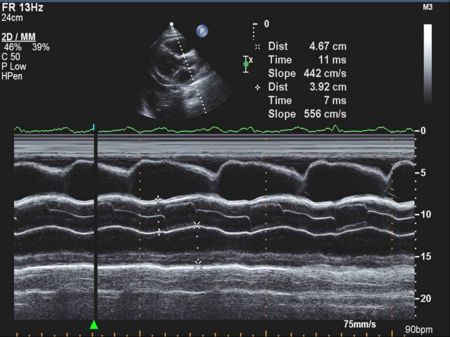

M Mode in Hypertrophic Cardiomyopathy

- Septal hypertrophy

- Systolic anterior motion (SAM) of the anterior mitral valve leaflet

- Mid-systolic (premature) closure of the aortic valve due to outflow track obstruction